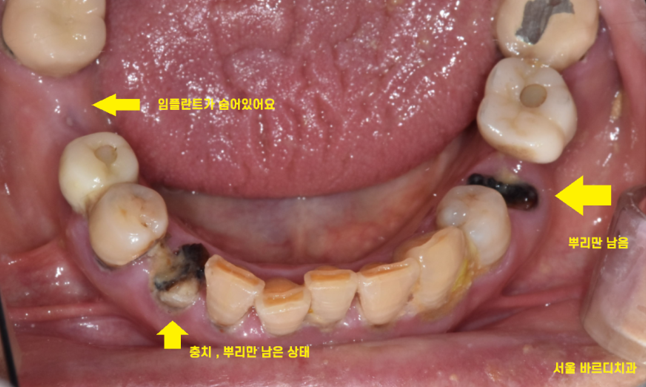

임플란트 머리 빠진 것 뿐만 아니고

뿌리만 남은 게 있어서

치료가 필요했습니다.

뿌리만 남은 부분은 발치 후 임플란트

여기저기 충치도 있고

뿌리만 남아있었는데 싹~ 치료하신 모습을 보니

뿌듯합니다.

깔끔해졌습니다.